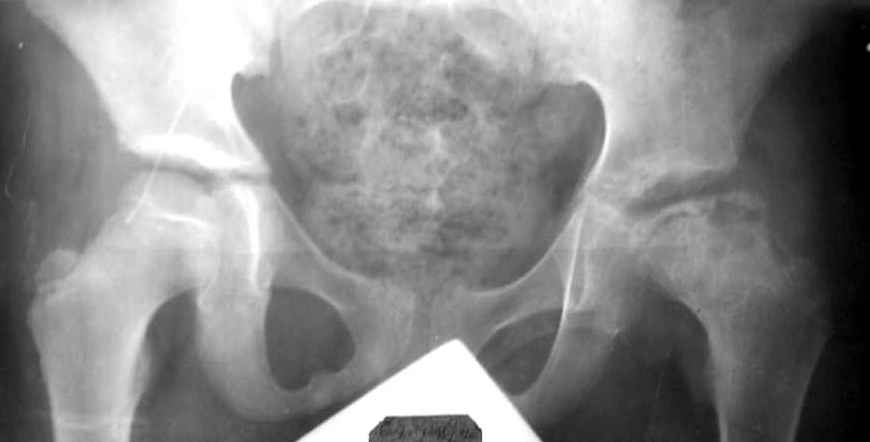

Мальчик 12 лет. Год назад по поводу асептического некроза, в субкапитальную область пересадил аутокостный трансплантат, взятый из Spina iliaca an.sup., на мышечной ножке m.sartorius.

На данный момент движения в суставе в полном объеме и без болезненны, ходит с помощью одного костыля, хотя, может спокойно передвигаться и без дополнительной опоры. Учитывая дисплазию, рекомендовал один костыль пока не бросать. Конечно, чем дольше он будет ходить на костылях, тем лучше для сустава, но ему всего 12, и он как все нормальные дети хочет бегать, прыгать, играть в футбол. Посоветуйте, пожалуйста, как быть? Заранее благодарю, Алишер.